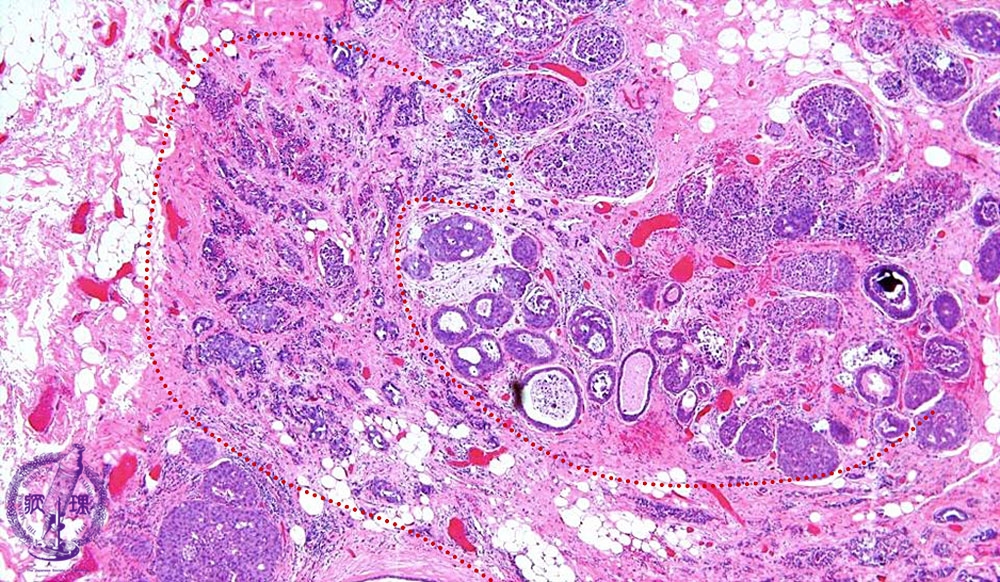

- 14.Breast

- ★(6)Invasive ductal carcinoma(Papillotubular carcinoma)

Microscopic image(HE stain, low power view):An example of well-differentiated type of invasive ductal carcinoma showing duct formation and/or papillary proliferation. In addition to intraductal spread, extensive stromal invasion (dotted line) is also apparent.